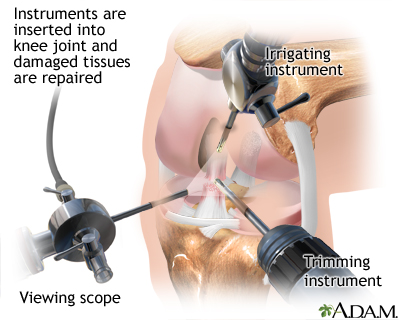

Severe cases of OA might benefit from surgery to replace or repair damaged joints. Options include:

- Arthroscopic surgery to trim torn and damaged cartilage